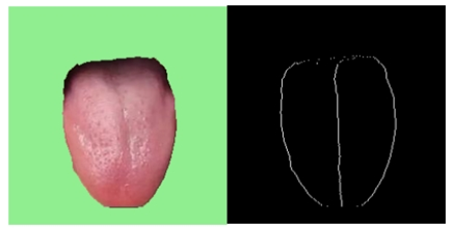

分析舌体的胖瘦最重要的一点是舌体是否摆正,即舌体的中轴线应与水平轴呈约为90°的夹角。若舌体过斜,那么后续的分析毫无意义。将分隔的舌体轮廓像素点进行标记,后计算像素矩阵中每一行像素点在水平轴上的平均坐标像素点。示例图如下:

实现效果如下如所示:

可见该段代码成功地标记出舌体的轮廓以及其“对称轴”~